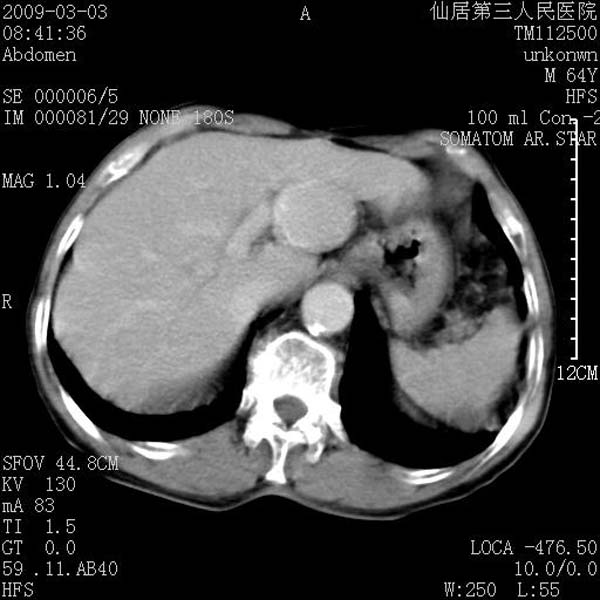

标题: CT18469:男性,64y,体检B超示肝脏低回声肿块,有胃溃疡手术 [打印本页]

标题: CT18469:男性,64y,体检B超示肝脏低回声肿块,有胃溃疡手术

患者,男性,64y,体检b超示肝脏低回声肿块,有胃溃疡手术史。

考虑----胃肠道间质瘤可能性大

从平扫及增强的特点来看,支持肝脏腺瘤并出血。

考虑胃间质瘤可能性大。

胃肠道间质瘤!

ct值呢?感觉没强化,象囊性。

考虑肝静脉韧带裂区良性占位性病变(囊肿?)。

考虑肝囊肿并出血可能性大.

考虑高密度囊肿可能性大